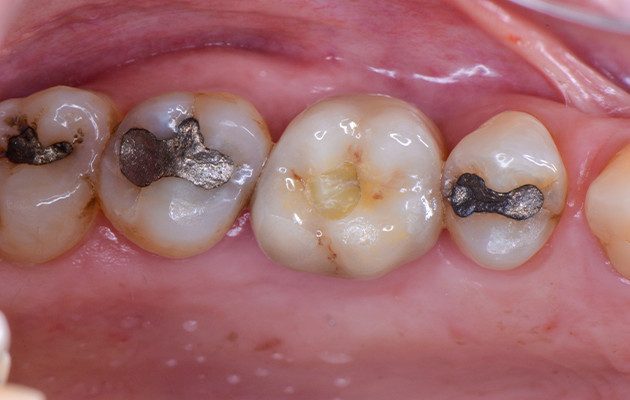

2 | Vista da superfície oclusal do dente 16. Nota-se a fratura das cúspides do dente, a restauração em amálgama de grande extensão, o acúmulo de biofilme e a presença de cárie abaixo da restauração.